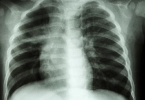

众所周知,心脏是人体非常重要的器官,生命活动要正常维持,必须保证心脏功能良好。许多人在心脏功能下降时会出现各种症状,影响正常生活。因此,平时要坚持好习惯养护自己的心脏。此外,当心脏病变时,身体会有明显的信号。那么,什么样的信号表明心脏在寻求帮助呢?

2、呼吸不畅

心脏发生病变时会发出求救信号,有些人在呼吸过程中感到呼吸不畅,总是感到气短,这种现象可能是心脏发出的求救信号。因为在心脏病的发展过程中,心脏所需的血液、营养物质等不能立即提供。

当心脏缺乏这些营养物质时,很容易降低心脏功能。心脏功能一旦下降,无法正常提供动力来维持血液循环,肺部所需的营养物质无法及时提供,可能会出现呼吸困难的感觉。